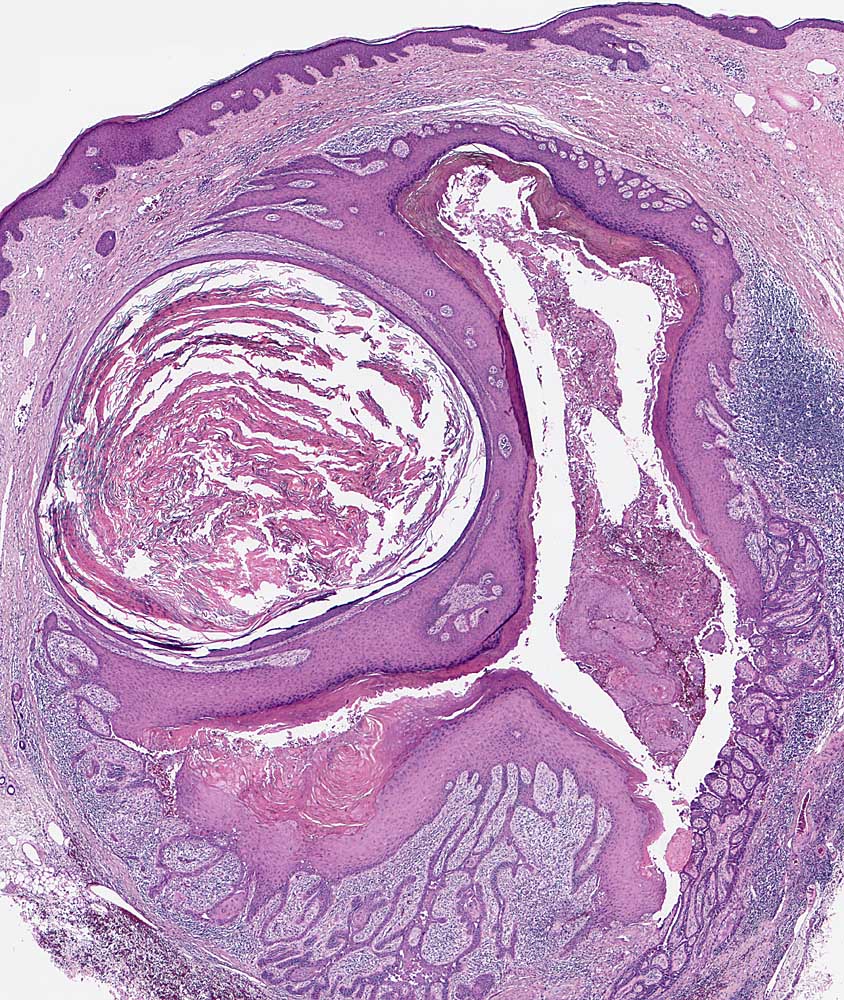

PathoPic ID 7208 - Warziges Dyskeratom

Warziges Dyskeratom

benigner Tumor

Haut, Rumpf

Haut

Epithelzyste des Haarinfundibulums mit fokaler Akantholyse. Orthokeratotische Hornmassen.

Graue hyperkeratotische Papel mit genabeltem Zentrum am Rücken.

Histologie

25